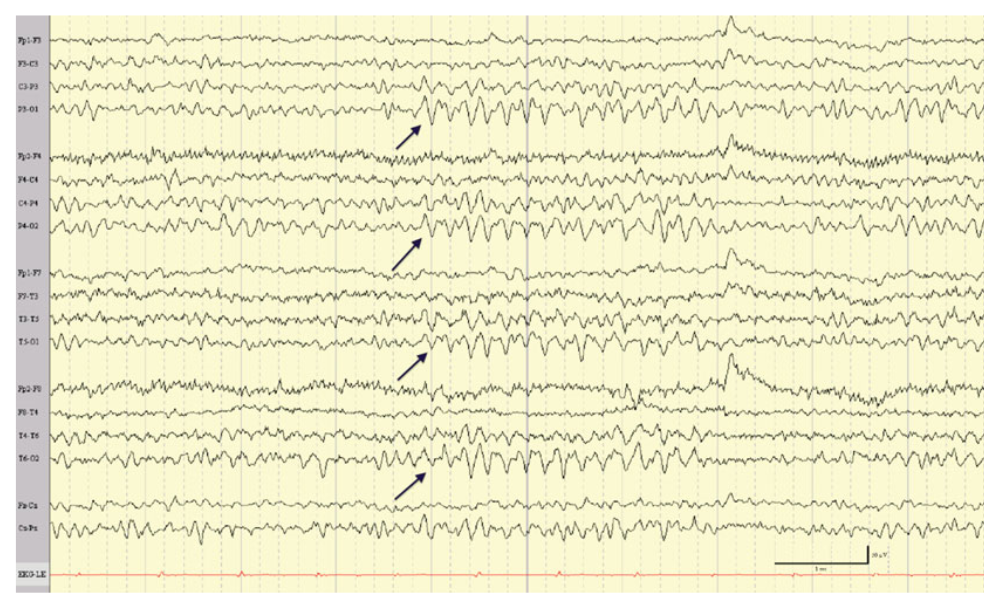

13

Q

• What

• who:

• when:

• Description

A

• what: SREDA

• who: >50 years

• when: rest / drowsiness / HV

• Sudden buildup of rhythmic monomorphic theta/delta, mostly in temporoparietal region